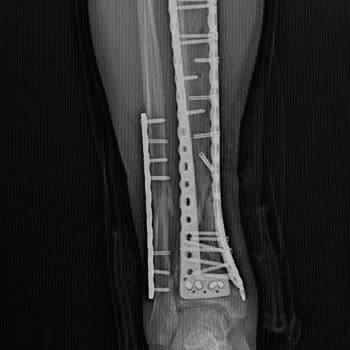

1994 yılında Şişli Etfal Hastanesi’nden görme engelim için aldığım %52 oranlı raporum süresiz verildi. 2004’te yine Şişli Etfal’den bu kez %55 oranlı, süresiz rapor aldım. Yıllarca tüm resmi işlemlerimi bu raporlara dayanarak yaptım, göz hastalığım nedeniyle askerlikten muaf tutulduğum için engel du...